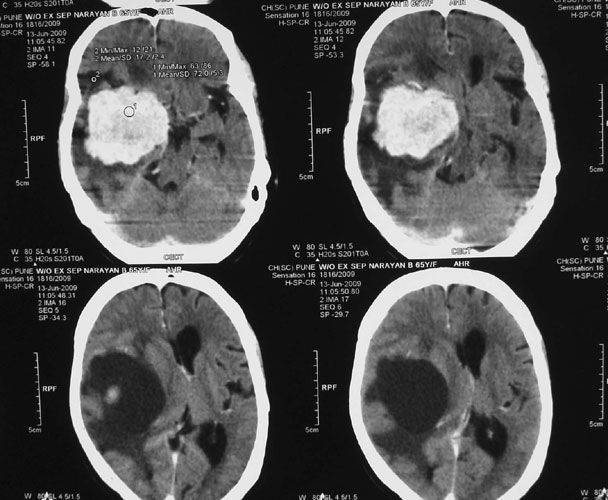

Arteriovenous malformations

Arteriovenous malformations of the brain are abnormal bunch of blood vessels that can rupture causing bleeding, or may cause seizures. Brain imaging (CT, MRI) is required for early diagnosis, while definitive treatment is carried out after cerebral angiography. Treatment implies craniotomy and excision of the AVM, which can be done safely in majority of the cases. Embolisation and radiosurgery are acceptable substitutes, but carry risk of further bleeding.